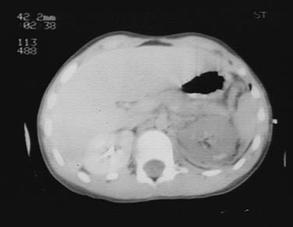

Hematom pelvian

Disjunctie de simfiza pubiana Disjunctie

de simfiza pubiana